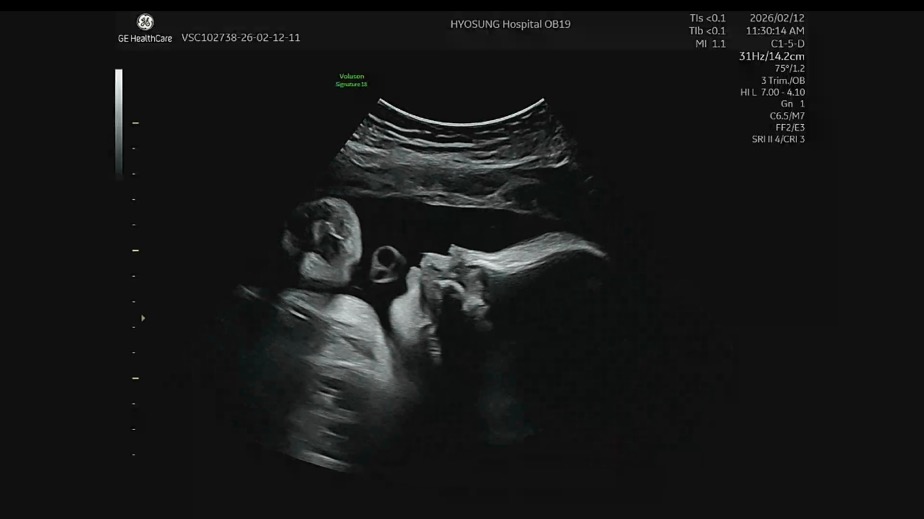

눈 코 입 보여 줌 💜

목에 탯줄이 두 번 감겨 있는데

크게 문제 될 건 아니라고…

자연분만 문제없이 할 수 있다고 하셨음

우리 아기 옆 모습 🤍 콧대 엄마 닮아라